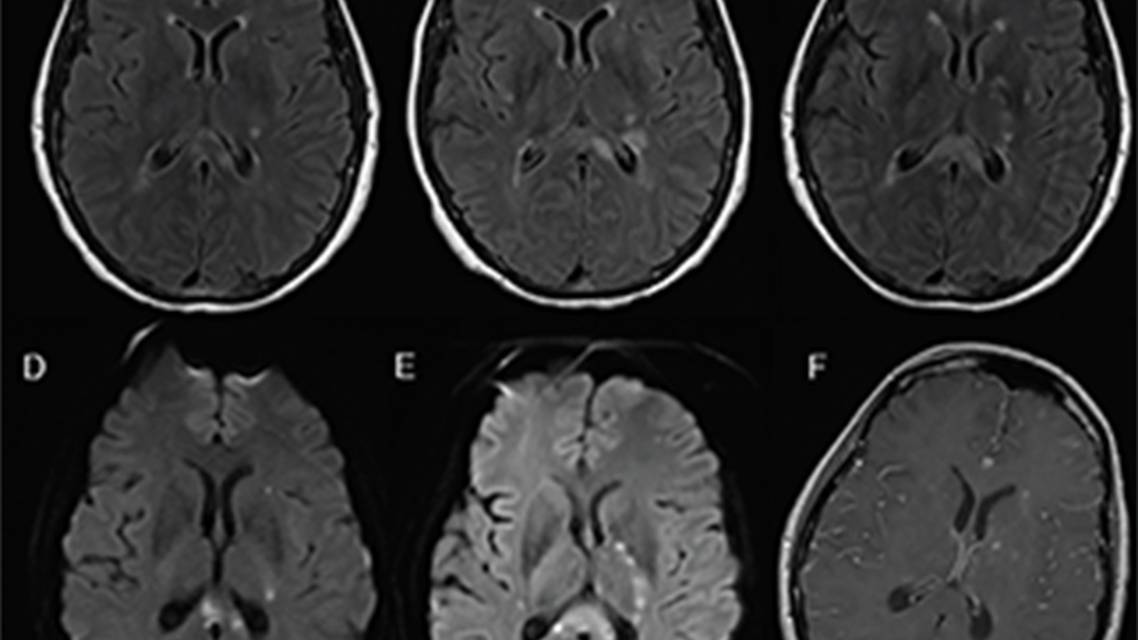

At Mrs. D’s first return, the previously placed loop had recorded no arrhythmia. Repeat MRI showed new infarcts in the left corona radiata and expansion of prior infarcts into the corpus callosum. After the new symptoms of hearing loss, dysarthria, and confusion developed, repeat MRI revealed additional multifocal acute infarcts involving both cerebral hemispheres and multiple areas of leptomeningeal enhancement (Figure).

B. The triad of encephalopathy, sensorineural hearing loss, and visual distortion should prompt consideration of Susac syndrome, in which autoimmunemediated occlusion of vessels in the brain, retina, and inner ear is thought to be responsible for this triad of symptoms. Very few people, however, present with all components of the triad initially.2,3 Characteristic neuroimaging findings are the triad of white matter lesions, (with preferential involvement of the central corpus callosum), deep gray matter lesions, and leptomeningeal enhancement, as seen on Mrs. D’s MRI.1